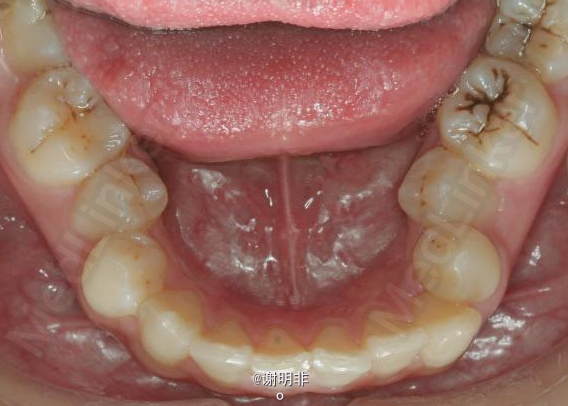

又一例不对称拔牙

牙弓狭窄,牙列拥挤